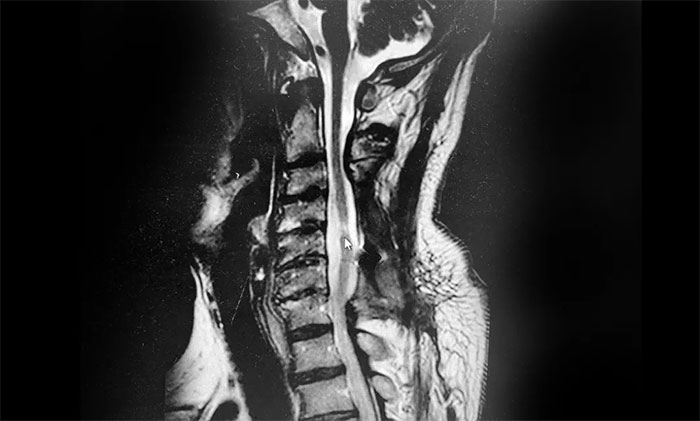

到就近医院救治,急诊查颈椎CT示:患者颈3-7椎体略变扁、颈椎反弓、项韧带钙化。颈椎脊髓损伤发生四肢瘫痪者,往往病情严重,常发生呼吸系统并发症,病死率高,对其治疗刻不容缓。其后,老刘转外院立即接受了颈椎后路减压融合内固定手术。

▲患者颈髓损伤、颈椎反弓